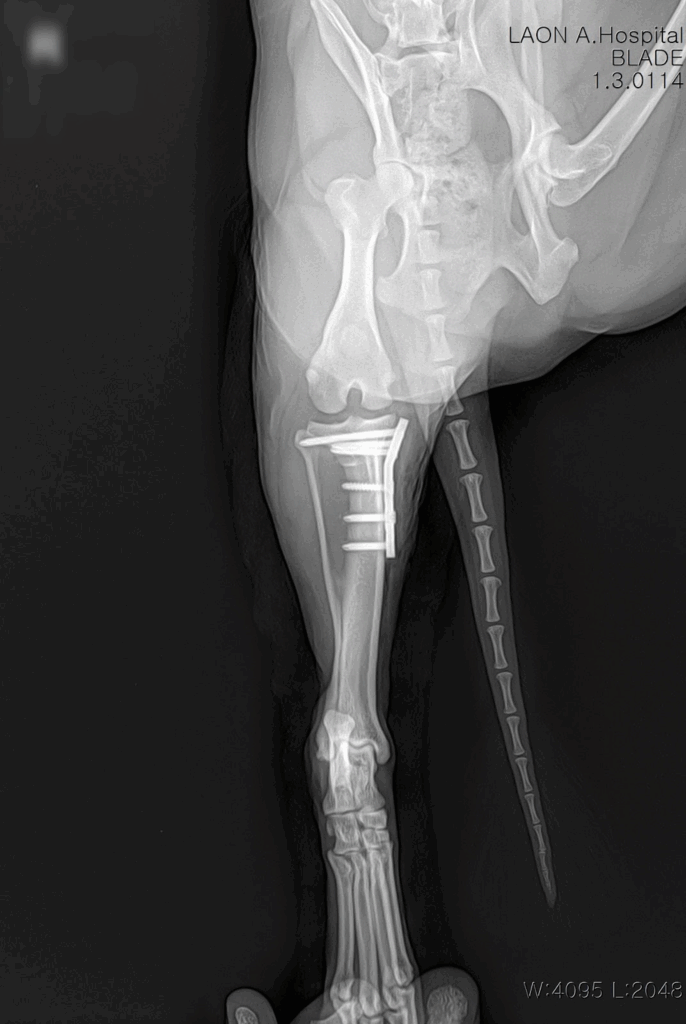

수술은 마취 안정 하에 무사히 마무리되었고, 절개 부위 봉합 후 감염 방지와 회복을 위한 집중 치료가 이어졌습니다.

수술 후 방사선사진 / 출처: 라온동물메디컬센터

수술 후 약 1주간 입원 치료를 진행하며 초기 재활 프로그램도 함께 시작했습니다. 재활 초반에는 통증 조절과 부기 완화에 중점을 두고, 점차 체중 부하 훈련 및 관절 운동 범위 회복을 도왔습니다. 이 사례에서 알 수 있듯, 대형견은 단 한 번의 무리한 동작으로도 파열이 발생할 수 있으므로 사전 예방이 무엇보다 중요합니다.